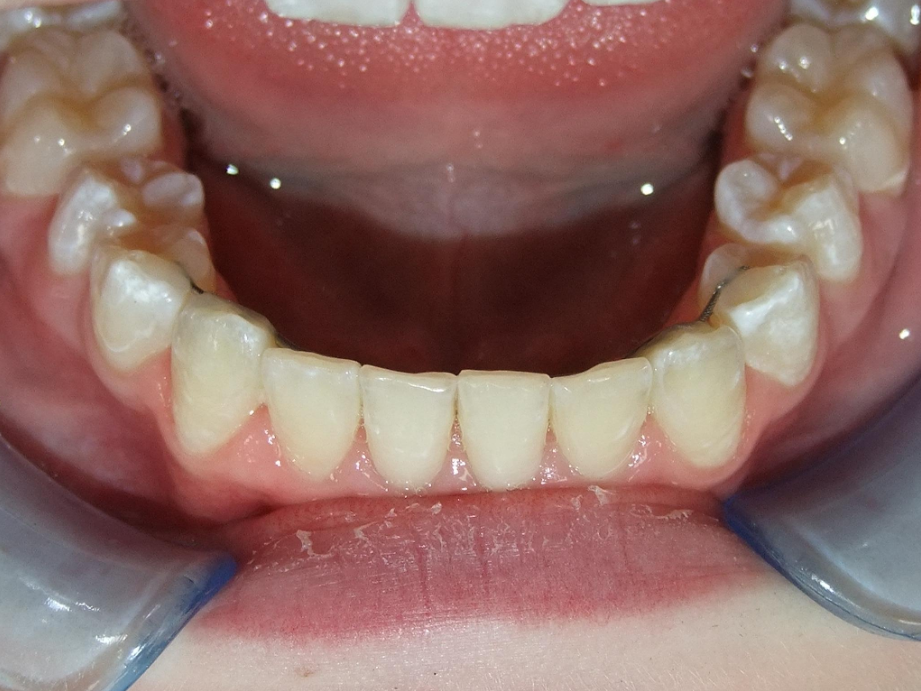

eindfoto

Leeftijd bij aanvang: 9 jaar

1-6 Bonded Hyrax + volledig vast onderkaak + TransForce onderkaak

7-13 Twin Block

14-28 volledig vast onder- en bovenkaak + rotator

Retentie: Wrap-Around

Leeftijd bij retentie: 12 jaar